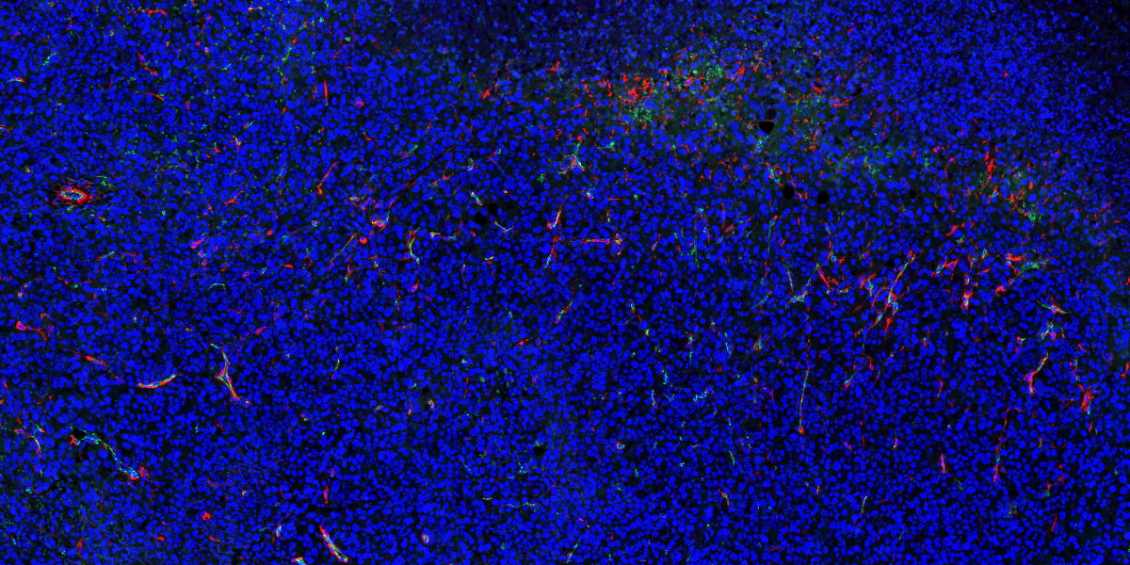

新疆石蜡切片免疫荧光不可避免会产生自发荧光。

1.取材的时候灌注取材,把红细胞冲洗干净;

2.脱蜡必须彻底,封闭、洗涤等过程也需充分;

3.抗体在使用前最好先离心处理并尽量从上方吸取,抗体的浓度过高也会产生自发荧光,所以可以预实验摸清最合适的抗体浓度再进行正式实验;

4.如若自发荧光很强,严重影响染色效果,亦可采用自发荧光去除剂进行去除。